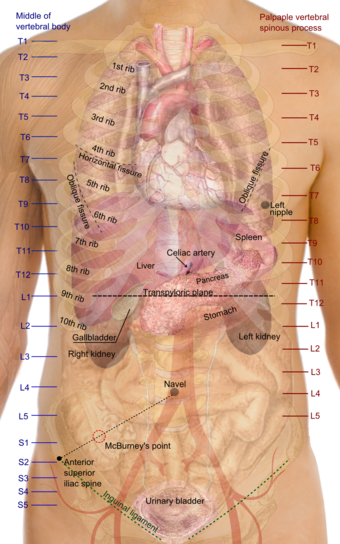

Location

In humans the kidneys are located in the  abdominal cavity, more specifically in the paravertebral gutter and lie in a  retroperitoneal position at a slightly oblique angle. There are two, one on each side of the spine. The asymmetry within the abdominal cavity caused by the  liver typically results in the right kidney being slightly lower than the left, and left kidney being located slightly more medial than the right. The left kidney is approximately at the vertebral level T12 to L3, and the right slightly lower. The right kidney sits just below the  diaphragm and posterior to the  liver, the left below the diaphragm and posterior to the  spleen. Resting on top of each kidney is an  adrenal gland. The upper (cranial) parts of the kidneys are partially protected by the eleventh and twelfth  ribs, and each whole kidney and adrenal gland are surrounded by two layers of fat (the perirenal and pararenal fat) and the  renal fascia. Each adult kidney weighs between 125 and 170 grams in males and between 115 and 155 grams in females. The left kidney is typically slightly larger than the right kidney.